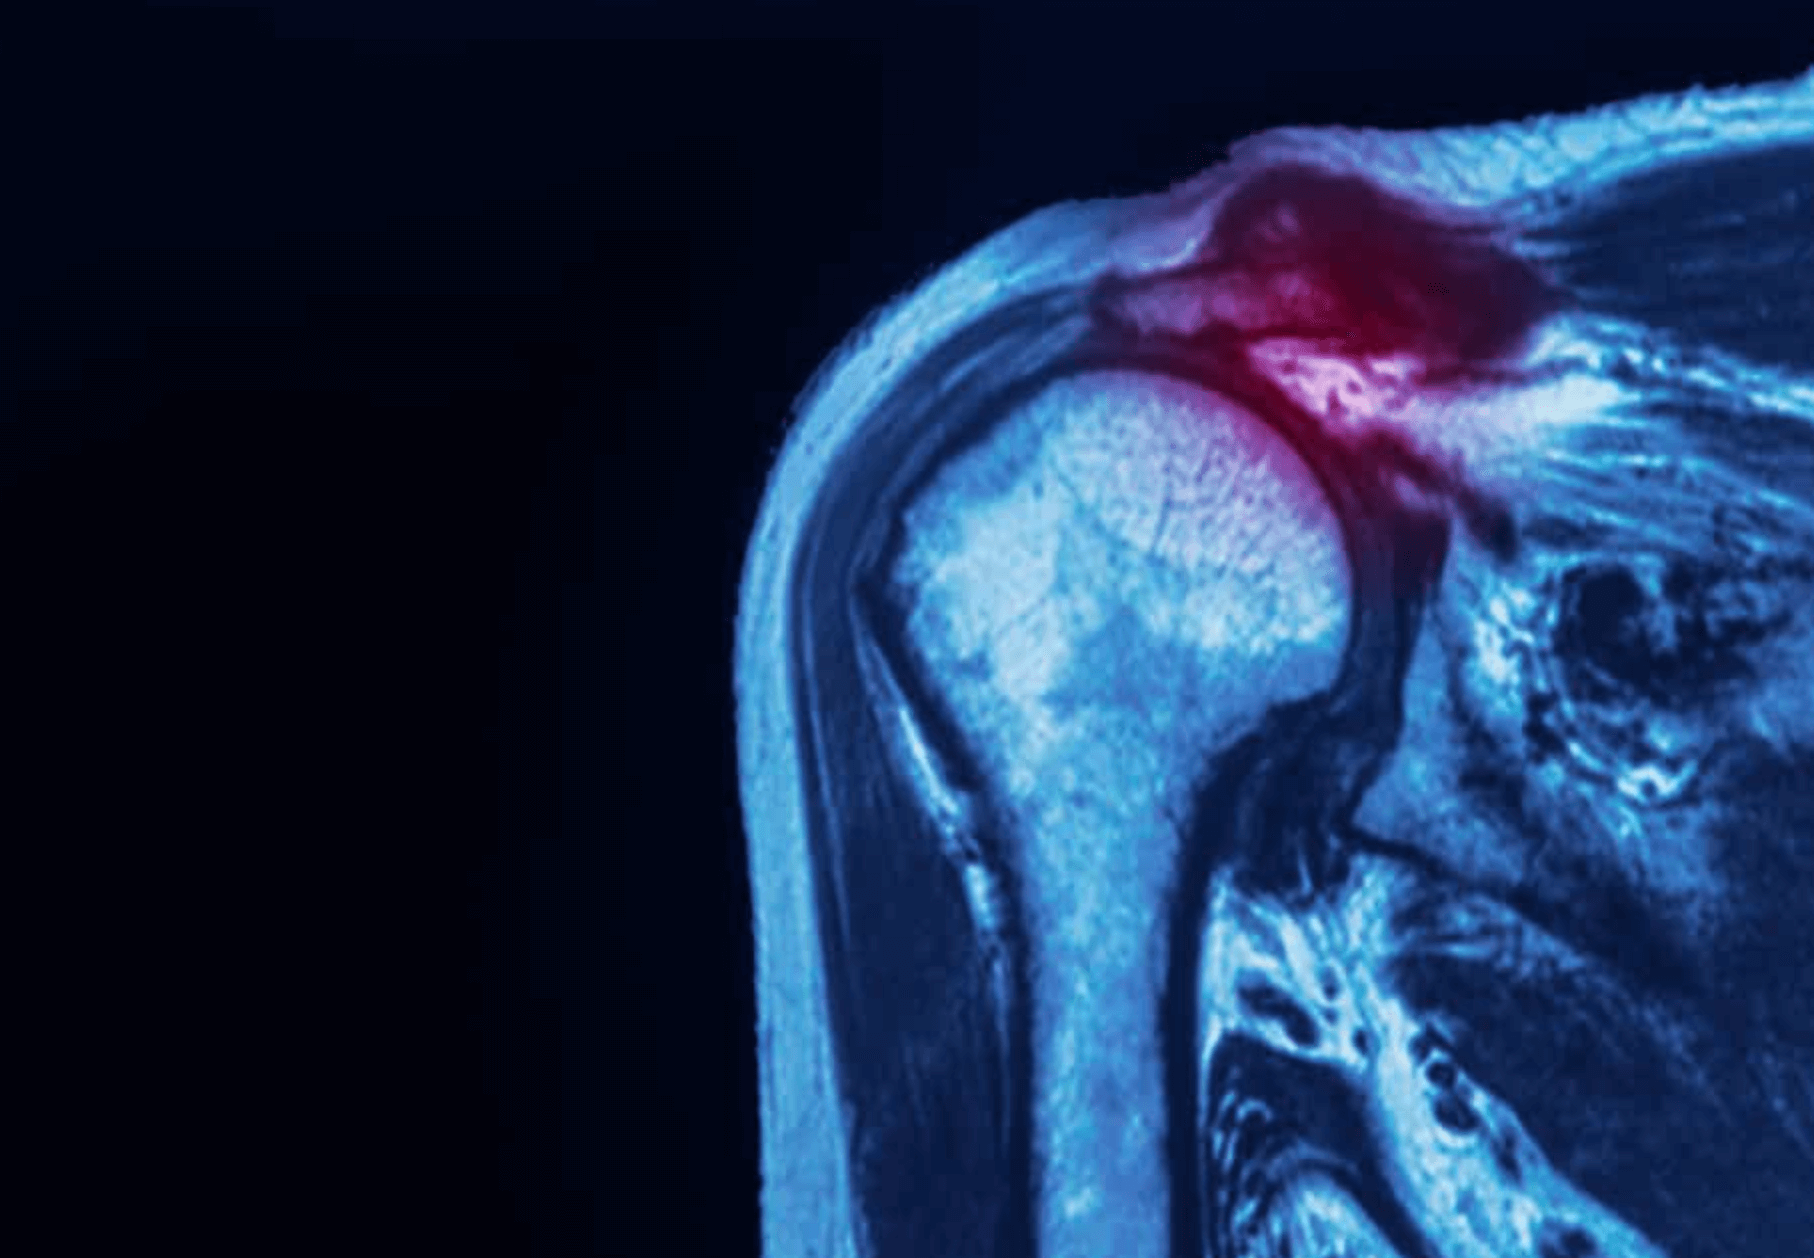

어깨 회전근개 부분파열

회전근개는 어깨에 있는 근육과 힘줄의 집합체라고 생각하면 됩니다. 회전근개 파열은 힘줄이 팔뼈에서 멀어질때 발생하고 과도한 사용이나 부상으로 인해 찢어질수 있습니다.

- 어깨 회전근개 부분파열 - 불완전하거나 부분적으로 찌어진 상태에서 힘줄은 팔뼈에 조금씩 붙어 있음

- 어깨 회전근개 파열 - 전층 또는 완전 파열로 힘줄이 뼈에서 완전 분리된 상태이며, 힘줄에 구멍이나 찢어진 부분이 있는 상태